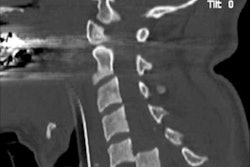

Demand is growing for emergency CT scans of the cervical spine, and because many examinations are performed at night or on weekends, often radiology trainees end up reporting them, U.K. researchers said. To speed up patient care and cut errors, they looked at how to improve training in this area, focusing on seven key learning points. Click here to find out more.